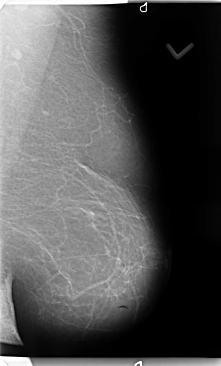

B_3135_1.RIGHT_MLO

RIGHT_MLO LINES 4696 PIXELS_PER_LINE 2712 BITS_PER_PIXEL 12 RESOLUTION 50 OVERLAY

FILE: B_3135_1.RIGHT_MLO.OVERLAY

TOTAL_ABNORMALITIES 2

ABNORMALITY 1

LESION_TYPE MASS SHAPE IRREGULAR MARGINS SPICULATED

ASSESSMENT 4

SUBTLETY 5

PATHOLOGY MALIGNANT

TOTAL_OUTLINES 1

BOUNDARY

ABNORMALITY 2

LESION_TYPE MASS SHAPE IRREGULAR MARGINS ILL_DEFINED

SUBTLETY 4

PATHOLOGY UNPROVEN